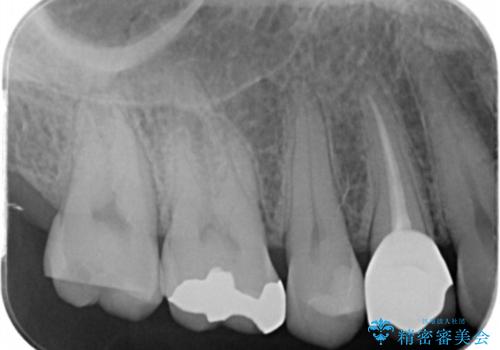

- 奥の歯に穴が空いているとの事で来院。

拡大鏡下で虫歯を全て除去しゴールドインレーにて治療しました。